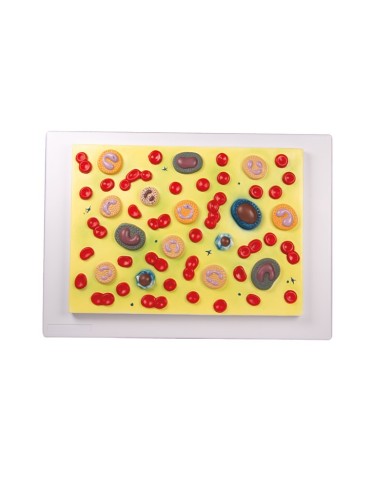

Su tavola, con supporto e istruzioni per l'insegnamento. Con colorante rosso e siringa di riempimento.

Realizzato in stampa 3D ad elevatissima risoluzione a colori.

Realizzato in stampa 3D ad elevatissima risoluzione a colori.

Realizzato in stampa 3D ad elevatissima risoluzione a colori.